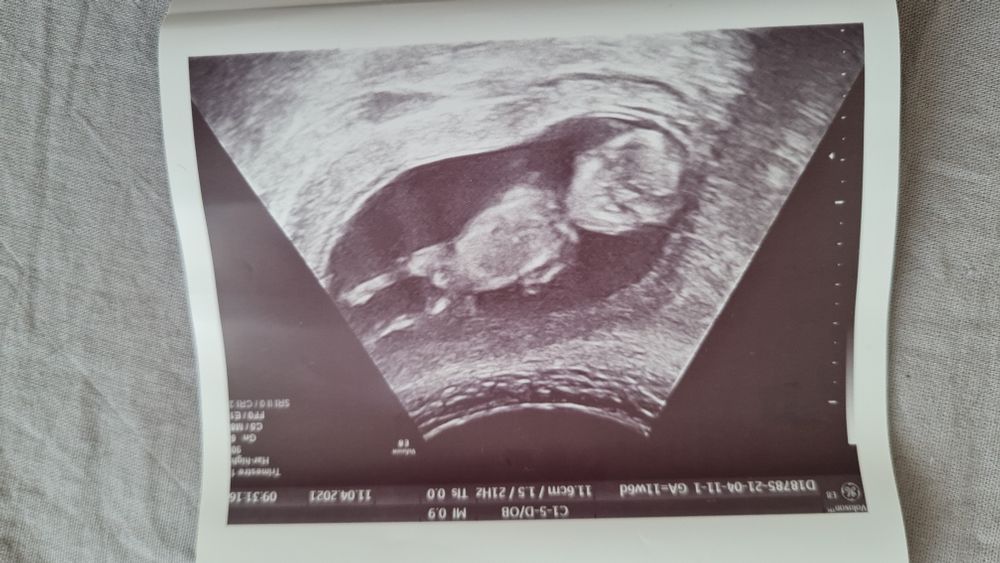

Узи 12 недель

Срок ровно 12 нед,по узи 12.4...КТР 61см, сердцебиение 165

На первом фото непонятно то-ли бугорок то-ли пуповина... Врач сказала непонятно совсем,может больше и к мальчику) так долго ждать ещё до 20 нед)))